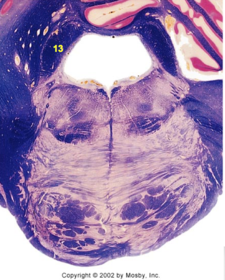

| Hypoglossal nucleus | |

| Hypoglossal nerve | |

| Dorsal motor nucleus of X | |

| Nucleus ambiguus | |

| Solitary tract | |

| Solitary nucleus | |

| ALS | |

| Medial lemniscus | |

| Medial longitudinal fasciculus | |

| Spinal tract of V | |

| Spinal nucleus of V | |

| Lateral (external, accessory) cuneate nucleus | |

| Medullary pyramids | |

| Anterior spinocerebellar tract | |

| CN IX | |

| Inferior cerebellar peduncle | |

| Inferior olivary complex | |